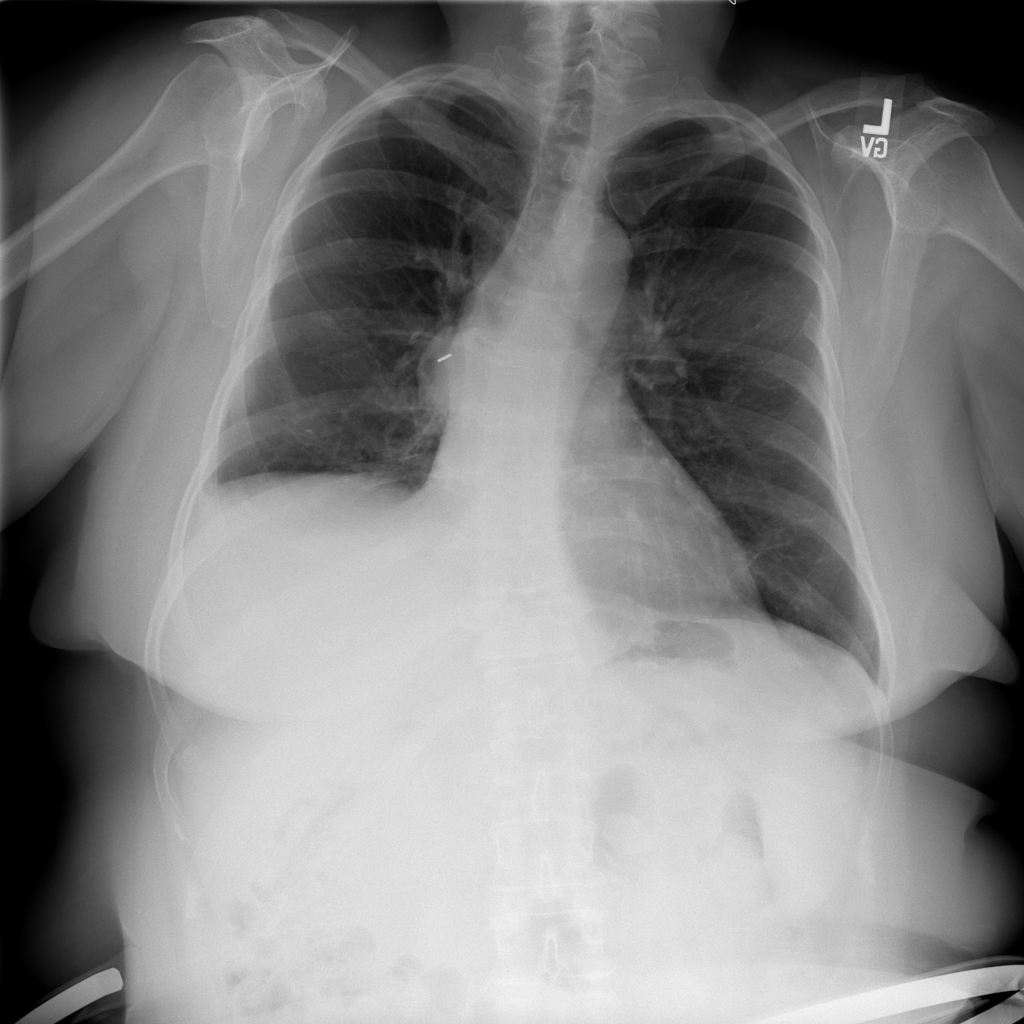

PAT-D7A5 · IMG-000Mass

PAT-D7A5 · IMG-000

PA